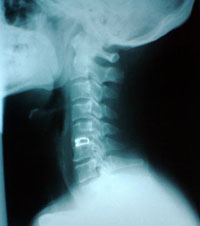

「むち打ち症」は追突された際に首がムチのようにしなるなるため「鞭打ち(むちうち)」と呼ばれます。

そのために首や背中・腰に過大な力が加わり、首の周りの筋肉・神経・靭帯・関節を傷め、捻挫の状態になり熱を発生します。特にその熱が神経を伝い、頭痛・めまい・痛み・しびれを発生させ、症状をひどくさせている原因になっています。

病院・整形外科でレントゲンやMRIなどの精密検査を受けましょう